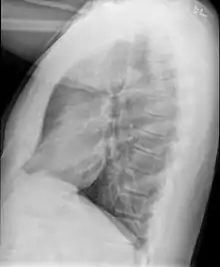

| High resolution CT scan showing bronchiolitis obliterans with mosaic attenuation, bronchiectasis, air trapping and bronchial thickening[3] | |